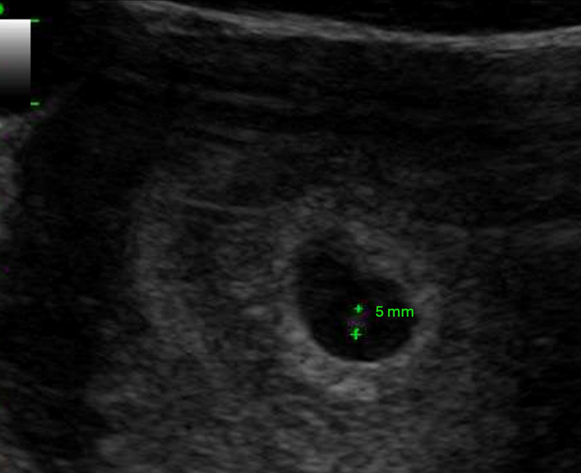

– testostérone : recherche d’une tumeur surrénale ou d’un syndrome des ovaires polykystiques (SOPK).